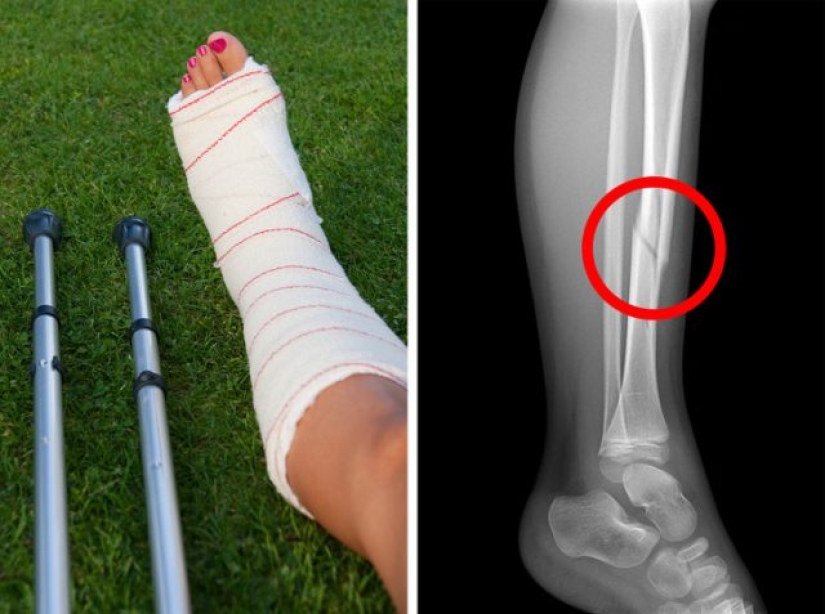

Calcium is essential for bone development and bone health, especially during childhood. However, all dairy products - or animal proteins in general - are acidic, which reduces calcium intake. Research shows that women who drink 3 or more glasses of milk a day have a higher risk of fractures.